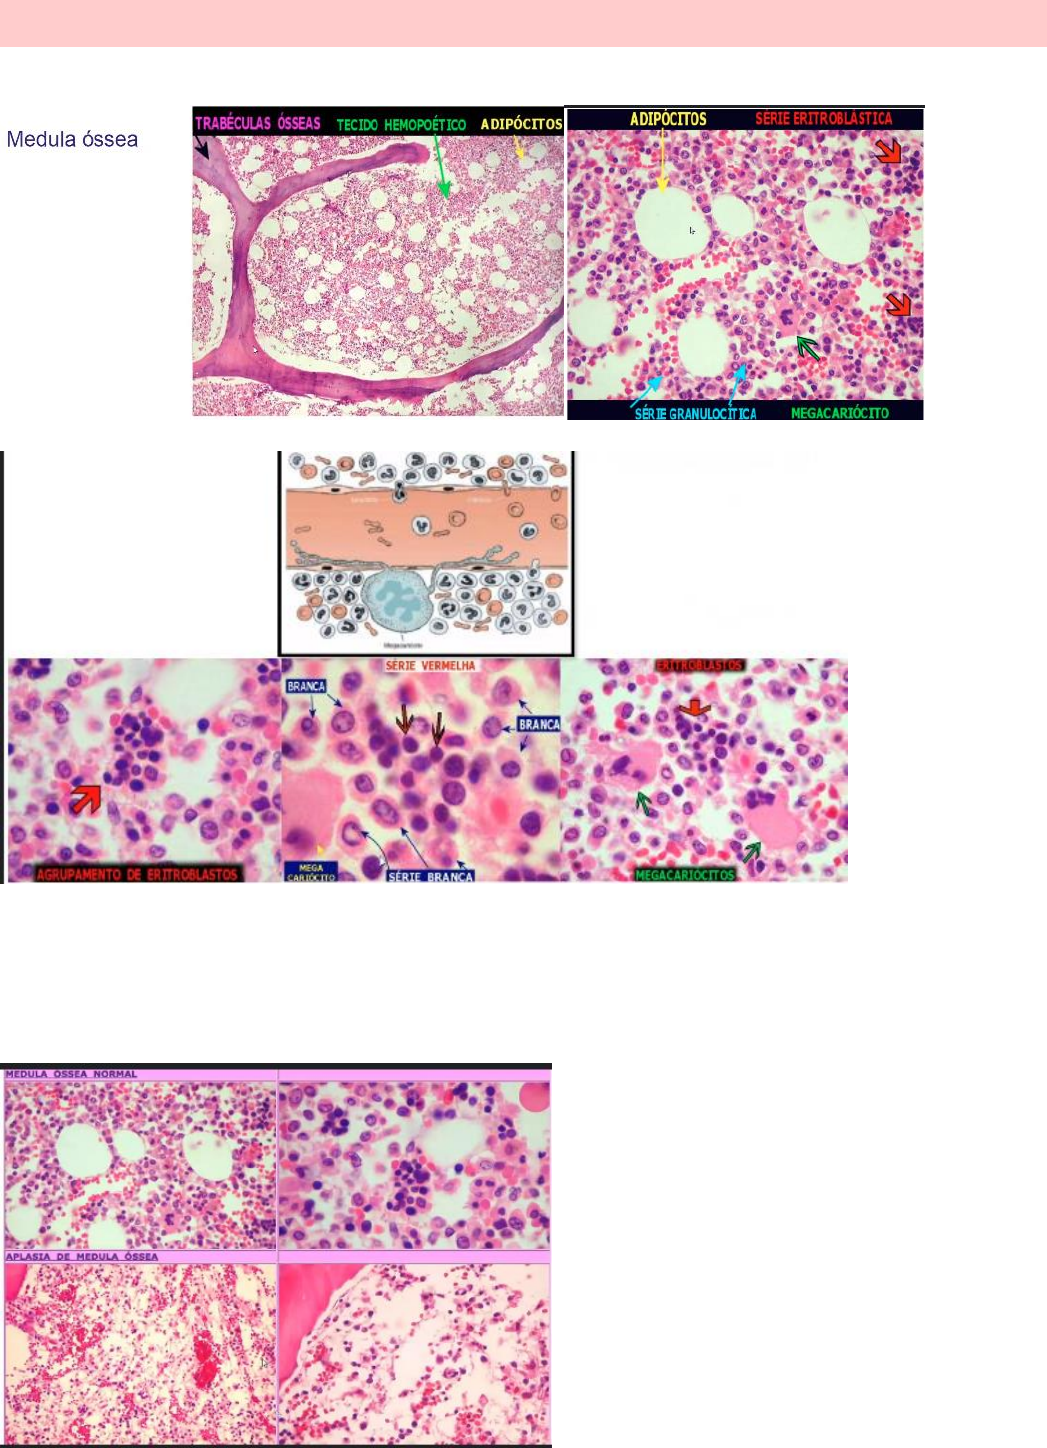

ANEMIA APLÁSICA

Ocorre a falência das 3 linhagens celulares: leucócitos, trombócitos e eritócitos (plaquetas, hemácias e glóbulos

brancos).

A medula óssea fica contida por várias células adiposas no estroma.

As células eritroblásticas tendem a hipercromatismo. Já os leucócitos apresentam núcleos menos corados e citoplasma

mais branco. Assim, evidencia a liposubstituição com perda de tecido medular por células de tecido adiposo e

linfócitos.

A Biopsia é padrão ouro para o diagnóstico (quando faz punção não vem nada de medula

óssea).

OBS: Anemia aplásica NÃO resulta em leucemia, pois ela não forma célula, assim não tem como ter leucemia se não

tem célula nenhuma.